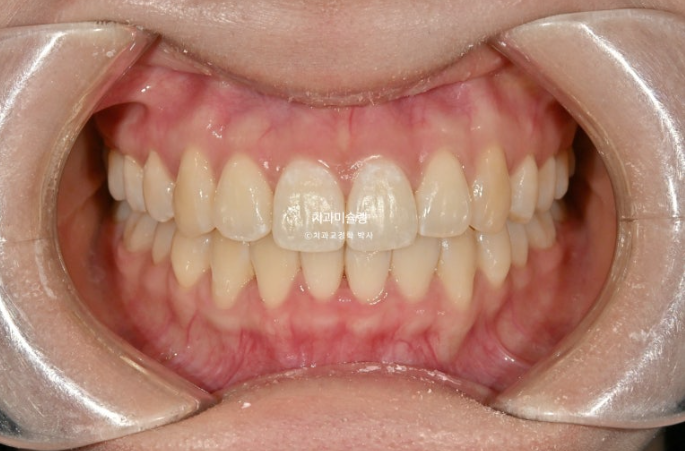

중심선은 정확히 맞고

어금니 교합은 물샐틈 없는 1급 교합관계 입니다.

이제 전 후 비교 보겠습니다.

총 치료기간은 1년 8개월 재제작은 1회 했습니다.